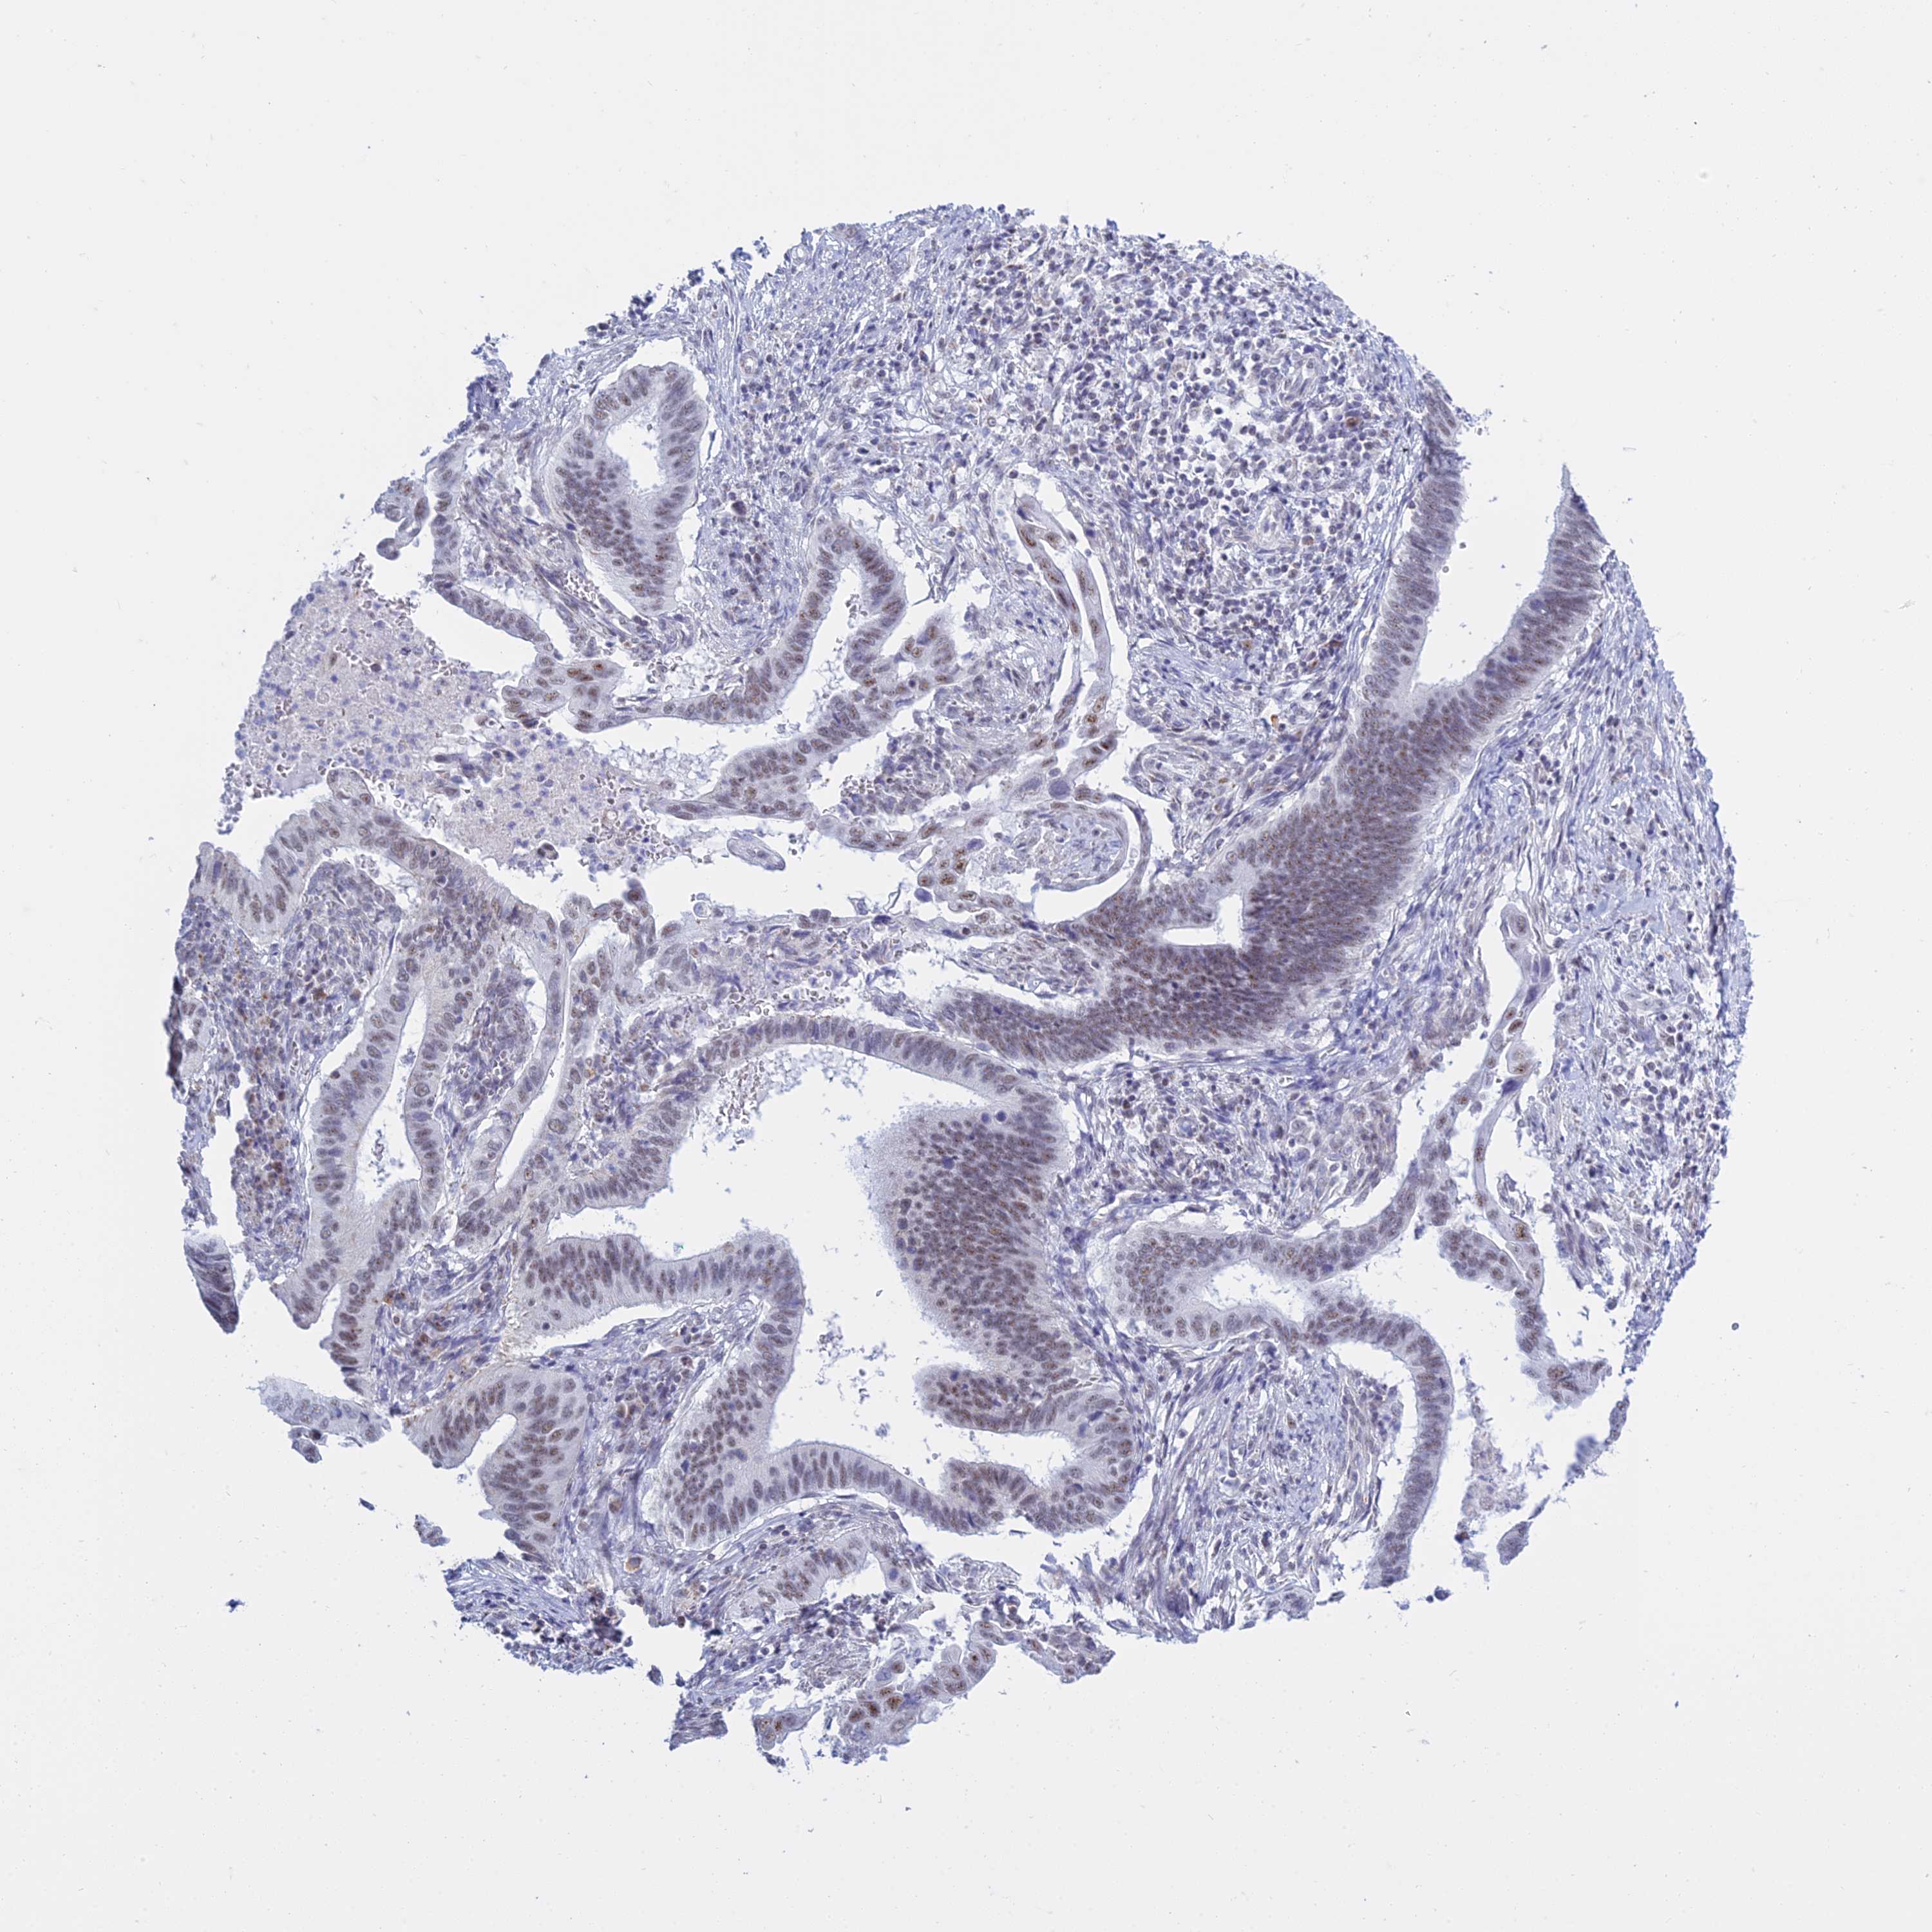

CERVICAL CANCER - Protein expressioni

A mouse-over function shows sample information and annotation data. Click on an image to view it in a full screen mode. Samples can be filtered based on level of antibody staining by selecting one or several of the following categories: high, medium, low and not detected. The assay and annotation is described here.

Note that samples used for immunohistochemistry by the Human Protein Atlas do not correspond to samples in the TCGA dataset.

Antibody stainingi

Antibody staining in the annotated cell types in the current human tissue is reported as not detected, low, medium, or high, based on conventional immunohistochemistry profiling in selected tissues. This score is based on the combination of the staining intensity and fraction of stained cells.

Each image is clickable and will lead to virtual microscopy that enables deeper exploration of all samples and also displays staining intensity scores, fraction scores and subcellular localization as well as patient and tissue information for each sample.

Antibody HPA044729

Staining

High

Medium

Low

Not detected

Intensity

Strong

Moderate

Weak

Negative

Quantity

>75%

75%-25%

<25%

None

Location

Nuclear

Cytoplasmic/membranous

Cytoplasmic/membranous,nuclear

Squamous cell carcinoma, NOS

Adenocarcinoma, NOS